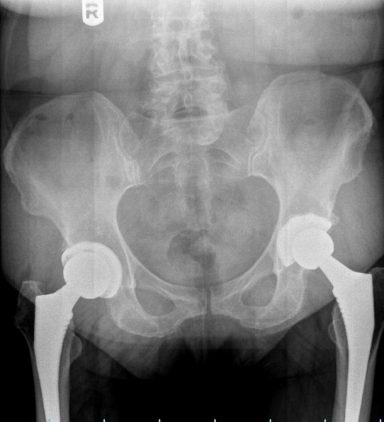

In this series, medical scans—MRI images, X-rays, and other diagnostic views—are transformed into intimate portraits that merge the clinical with the deeply personal. Each work intertwines medical imagery with biographical details, creating a layered visual narrative that honors both the physical realities of illness and the inner lives of those who endure them.

The exhibition features representations of conditions such as multiple sclerosis, lung cancer, hip and knee replacements, a broken wrist, miscarriage, and heartache—each one a story of endurance, adaptation, and faith. The artist wishes to express her gratitude to the patients and their families who entrusted her with creating artworks as unique and special as they are while acknowledging that recovery is never an individual journey; it extends to loved ones who must also heal, grieve, and rediscover vitality in the face of loss or uncertainty.

Mixed media pieces of art derived from the combination of medical scans, surveys from family and friends and genuine creativity from the creator, these artworks are one of a kind.